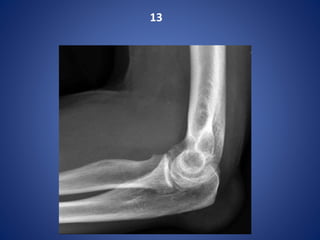

Olecranon bursitis- GOUT

X-rays of the left elbow demonstrate a soft tissue swelling overlying the olecranon. It is

somewhat hyperdense.

Deposition of sodium urate monohydrate crystals in synovial membranes, articular cartilage,

ligaments, bursae leading to destruction of cartilage